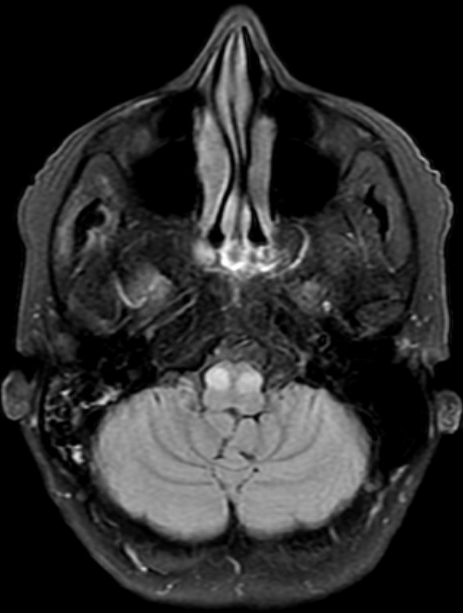

Results: The patient’s repeat brain MRI 4 months after the initial hemorrhage showed interval improvement in the hemorrhage and brainstem edema without an underlying mass. However, there was subsequent development of bilateral HOD (figure 1), more prominent on the right. Examination 5 months after the initial presentation showed a primarily horizontal head tremor, mild right torticollis, slight left laterocollis, slight left shoulder elevation, and mild retrocollis. Null point was achieved with turning the head fully in either direction, though more persistently suppressed with head turn to the left. There was also a low frequency postural tremor in the right arm that became most prominent in the wing-beating position. There were a few beats of uvular tremor noted when her mouth and palate were at rest. The option of botulinum toxin injections was considered, and after a detailed discussion of the risks, benefits, and alternatives with the patient, especially the risk of worsening baseline dysphagia, a joint decision was made to proceed cautiously with injections which yielded slight benefit without side effects and repeat injections were planned.

figure 1